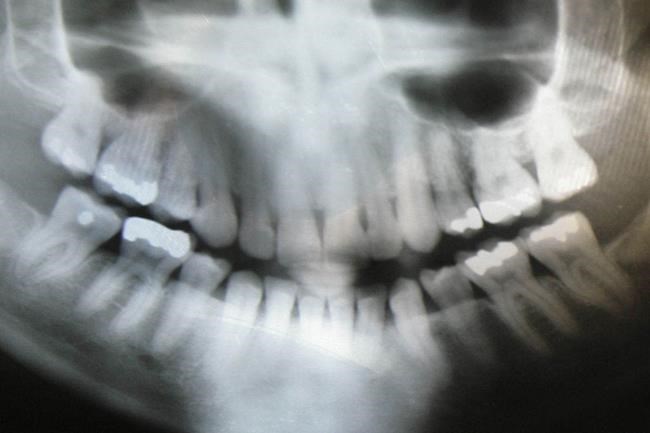

Getting a dental X-ray? A new recommendation says you don’t need a lead apron

Those heavy lead aprons may be on their way out at the dentist office, depending on where you live.

The nation’s largest dental association said Thursday it will no longer recommend the use of lead aprons and thyroid collars on patients who are getting dental X-rays.

There are two main reasons for the change. X-ray beams are now more focused, so there is less concern about radiation hitting other parts of the body. Also, the aprons and collars can sometimes block dentists from getting the images they need.